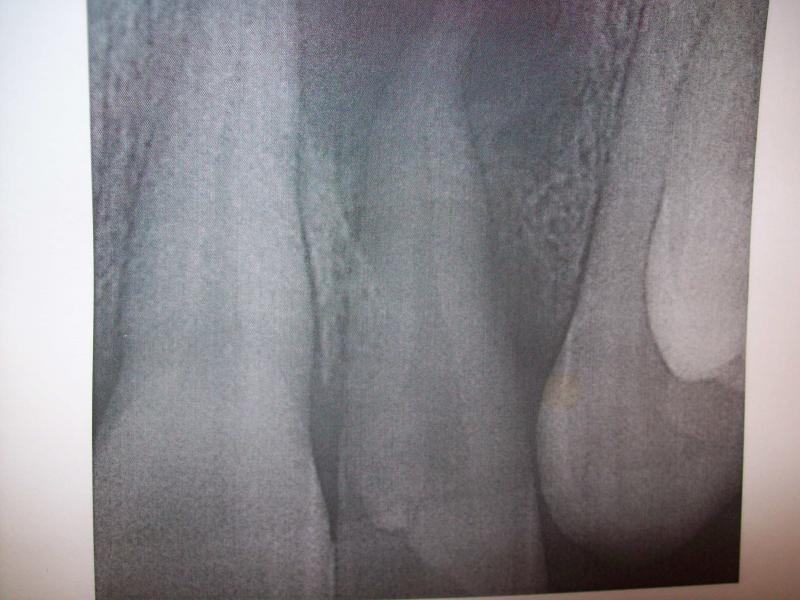

DR JET LOVES ROOT CANALS

General Dentist,  Performs Root Canals ONLY - Microscope Trained Dentist

"DR. JET'S MISSION IS TO PERFORM  ROOT CANALS FOR A REDUCED FEE USING THE LATEST TECHNOLOGY  AND TECHNIQUES TO SERVICE THE MANY PEOPLE WHO ARE UNINSURED OR UNDER-INSURED GIVING EVERYONE AN OPPORTUNITY TO SAVE THEIR TOOTH!"